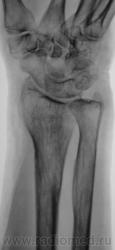

Травма.   Пациент направлен на рентгенографию лучезапястного сустава.

СЛУЧАЙ № 1.